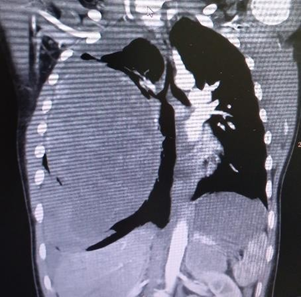

The child was in good general condition. Pulmonary auscultation showed hypoventilation of the right hemithorax, so a chest x-ray was performed, which revealed an increase in density in the lower 2/3 of the right hemithorax and displacement of the mediastinum to the contralateral side (Figure 1).

Figure 1 Preoperative chest X-Ray.